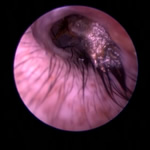

ポリープや腫瘤を伴う耳道炎と中耳炎

外耳炎が慢性化すると過形成、アポクリン腺腫瘍、炎症性ポリープ、鼻咽頭ポリープ(猫)などにより耳道が狭くなったり、閉塞することがあります。これが原因で外耳炎が治癒せず中耳炎に至るケースがよくあります。この状態になると生涯にわたり治療が必要になったり、根治には手術が必要になることもあります。